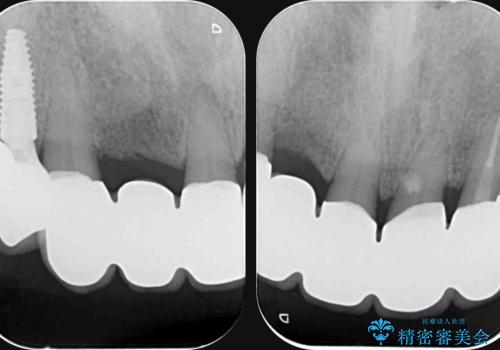

セラミック治療を行う前に歯周病の問題を解決すべく歯周外科を行い歯周ポケットを除去し整備したのちセラミックブリッジ・クラウンの製作を行います。

歯周外科を行ったことで非常に安定した歯周環境となり、引き締まった歯ぐきとなりました。